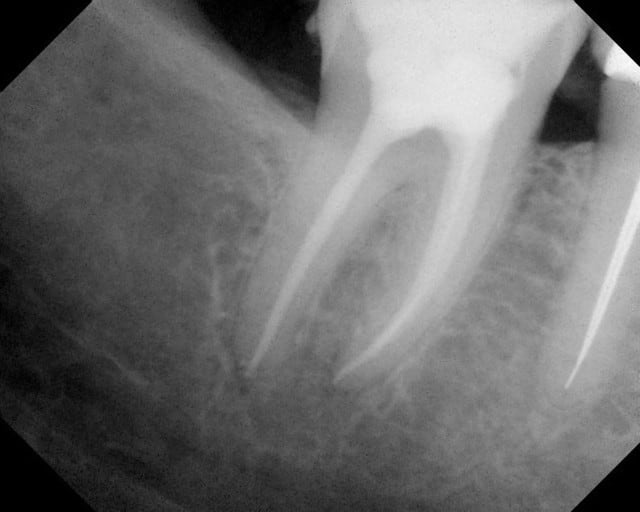

Tiens, un cas à moi: une dent dépulpée par mes soins qui casse au bout de 5 ans, sans tenon radiculaire. Et une autre obturée avec des cônes d'argent et un screw post qui a résisté après je ne sais combien d'années.

Est-ce que ça prouve que les cones d'argent et le scew post sont plus fiables que la gutta chaude et un composite sans tenon ?

Un cas clinique n'est qu'une anecdote, pas un preuve scientifique.

La cause d'un succès ou d'un échec endodontique n'est pas toujours ce qui saute aux yeux au premier abord